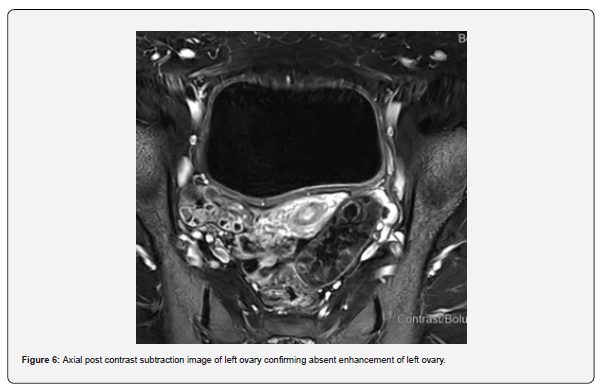

The patient is a 12-year-old girl who presented to emergency department with severe left-sided abdominal pain associated with persistent vomiting for the past two days. On physical examination left flank tenderness was noted with radiation to suprapubic area, there was no diarrhea or fever. Pelvic ultrasound with Doppler demonstrated bilaterally enlarged ovaries with small follicles with a markedly enlarged left ovary showing reduced vascularity and no evidence of identifiable ovarian cyst (Figures 1-4). Magnetic resonance imaging (MRI) demonstrated bilateral ovarian enlargement with multiple small follicles, assuming polycystic ovarian morphology. The left ovary was significantly enlarged, positioned posterior to the uterus and showed stromal edema with decreased post-contrast enhancement compared to contralateral side, findings consistent with ovarian torsion (Figures 5-10).

These anatomical and developmental factors, including increased ligamentous laxity and adnexal mobility have been documented as important risk factors for ovarian torsion in pediatric patients, even in the absence of large adnexal mass [6]. In the present case, intraoperative findings revealed a small ovarian cyst that was not detected on ultrasound or MRI. This discrepancy may be explained by torsion related ovarian edema, hemorrhage and distortion of normal ovarian anatomy, which can obscure small cysts on imaging studies. This case underscores that the absence of visible ovarian cyst on imaging does not exclude ovarian torsion and highlights the importance of correlating imaging findings with clinical presentation and clinical judgement.